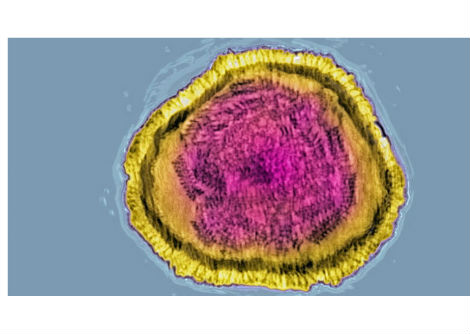

يظهر "تخطيط أمواج الدماغ" electroencephalogram نمط نوم الموجة البطيئة من النوم العميق لأحد المشاركين في الدراسة. قد تعزّز الاضطرابات في تلك المرحلة من النوم مرض الزهايمر.